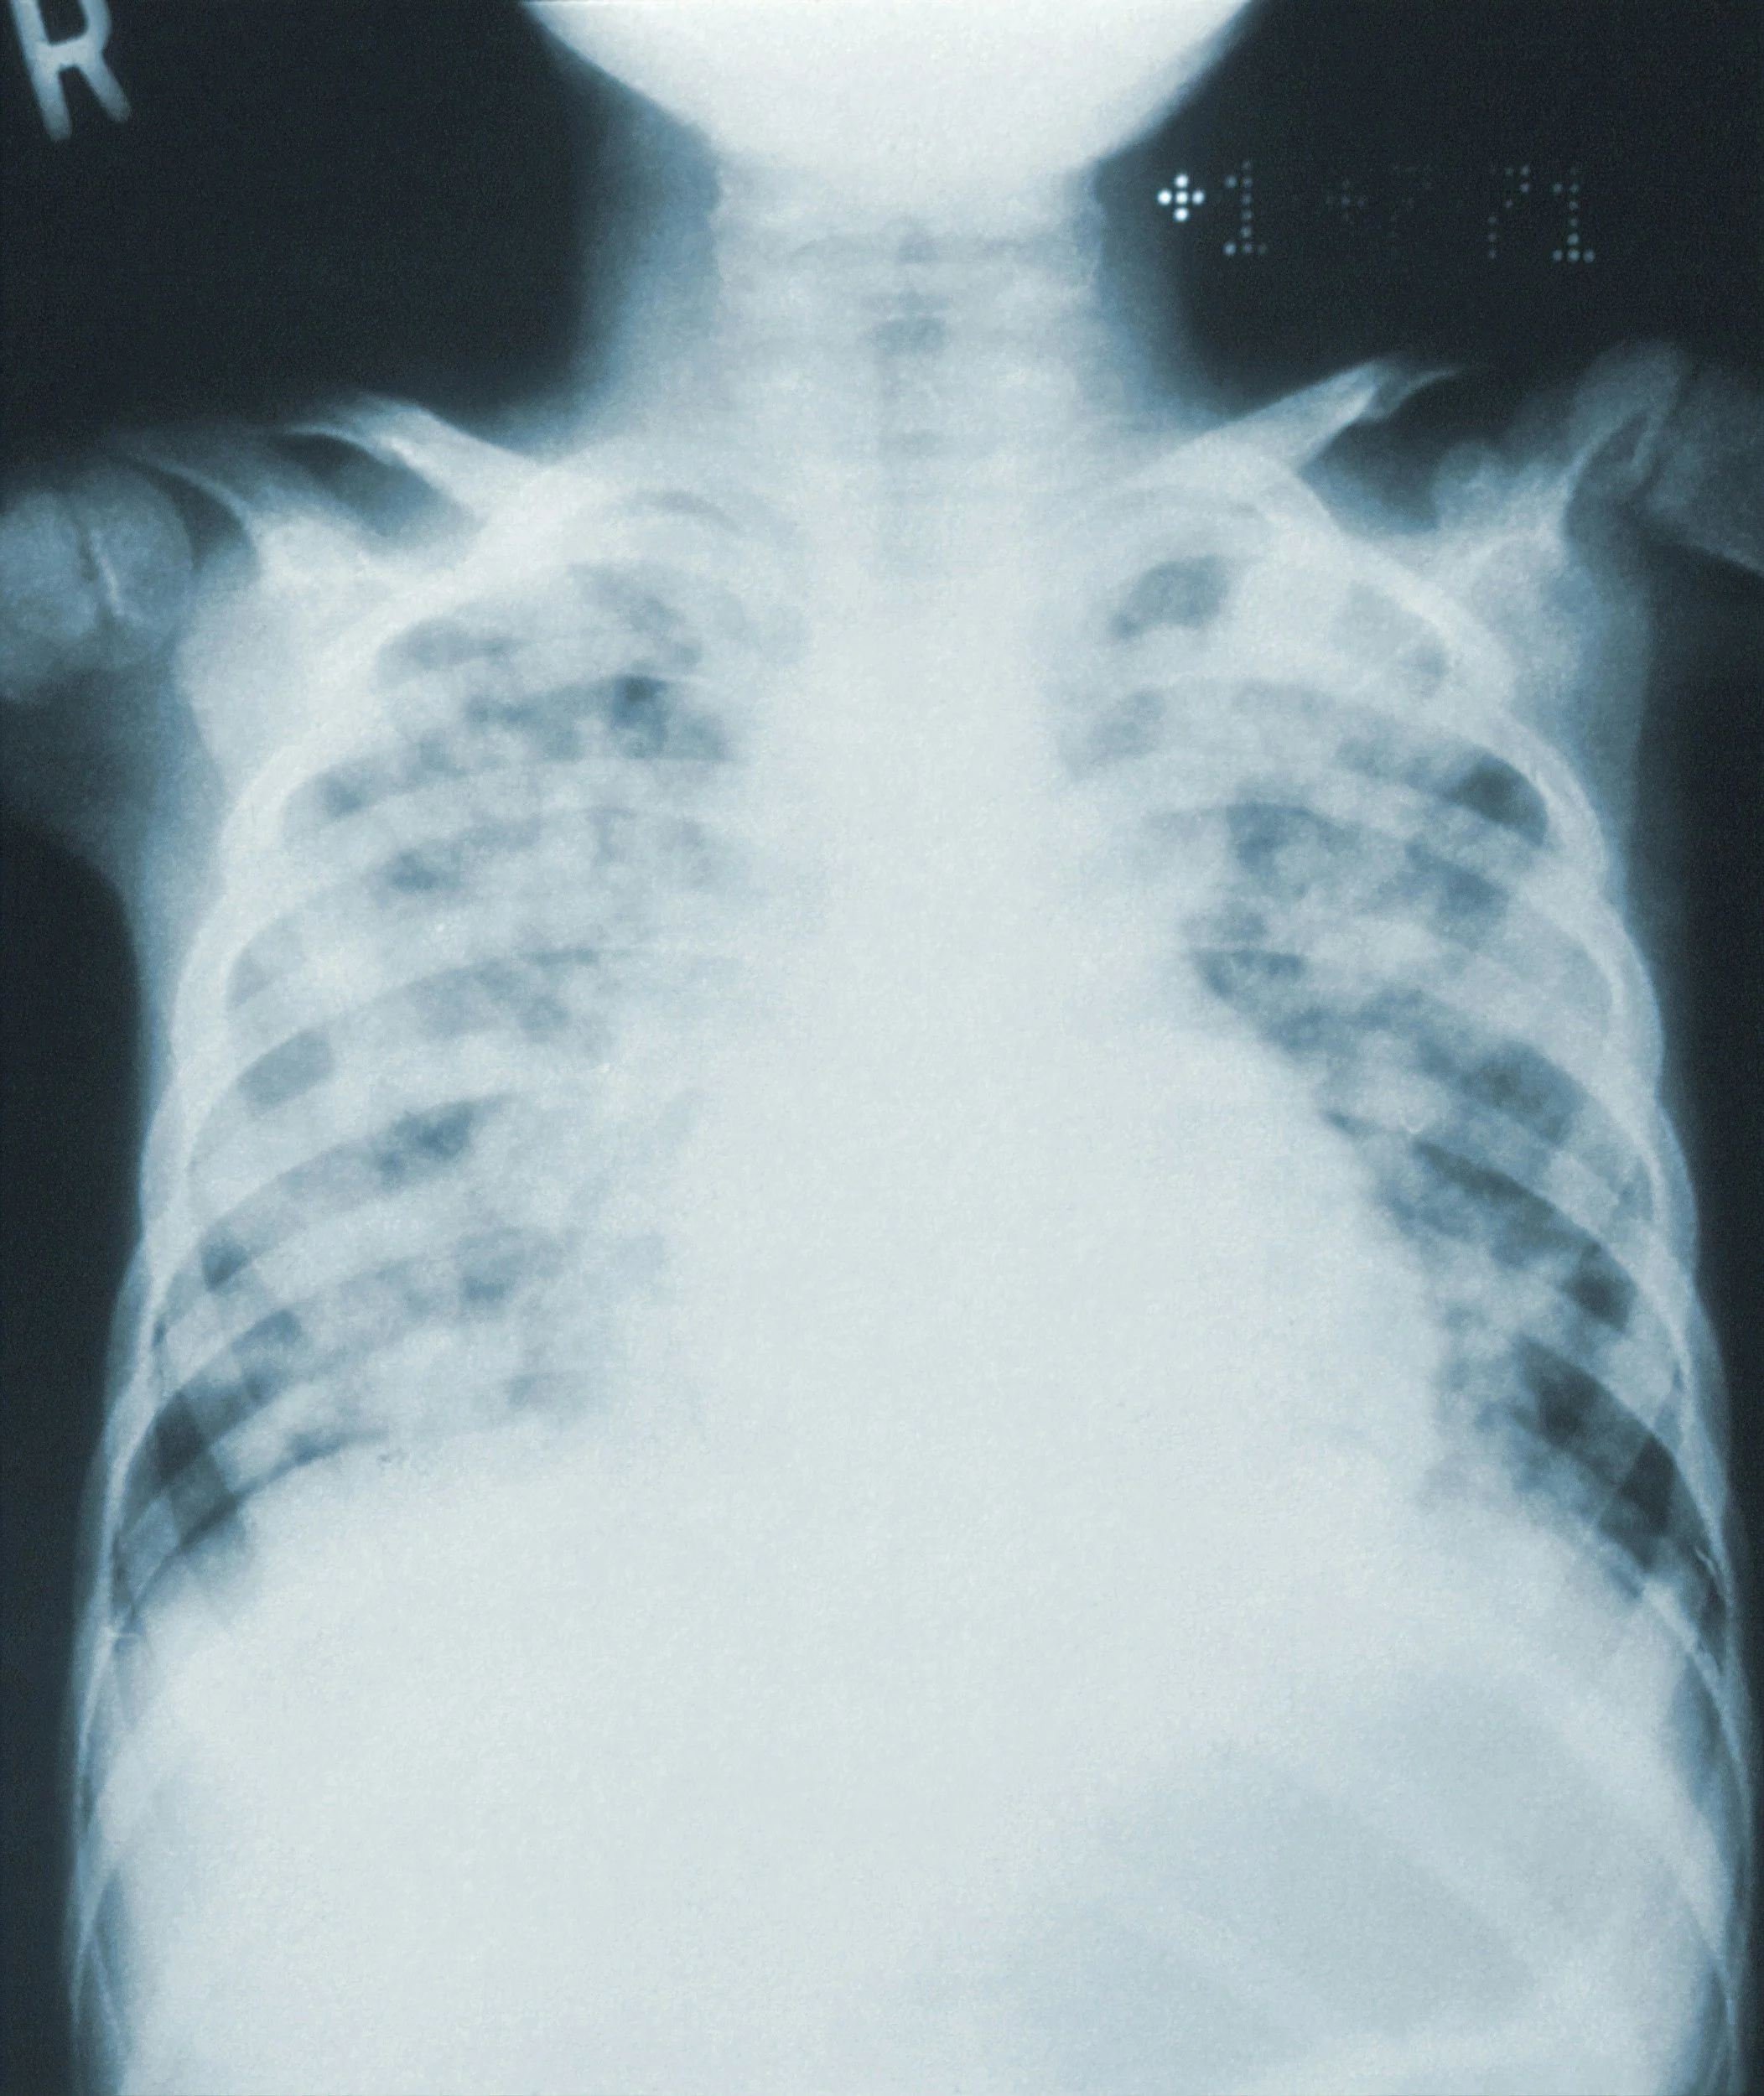

ARDS